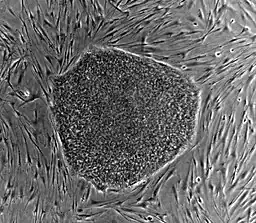

- Human embryonic stem cell colony on mouse embryonic fibroblast feeder layer

Nearly all research to date has made use of mouse embryonic stem cells (mES) or human embryonic stem cells (hES) derived from the early inner cell mass. Both have the essential stem cell characteristics, yet they require very different environments in order to maintain an undifferentiated state. Mouse ES cells are grown on a layer of gelatin as an extracellular matrix (for support) and require the presence of leukemia inhibitory factor (LIF) in serum media. A drug cocktail containing inhibitors to GSK3B and the MAPK/ERK pathway, called 2i, has also been shown to maintain pluripotency in stem cell culture.[25] Human ESCs are grown on a feeder layer of mouse embryonic fibroblasts and require the presence of basic fibroblast growth factor (bFGF or FGF-2).[26] Without optimal culture conditions or genetic manipulation,[27] embryonic stem cells will rapidly differentiate.